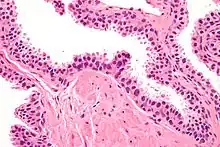

HGPIN typically has one of four different histologic patterns:[2]

- tufted (fascicular patterning)

- micropapillary,

- cribriform and,

- flat.

Its cytologic features are that of prostatic adenocarcinoma:

- presence of nucleoli,

- increased nuclear-to-cytoplasmic ratio and,

- increased nuclear size.

Microscopically, PIN is a collection of irregular, atypical epithelial cells. The architecture of the glands and ducts remains normal. The epithelial cells proliferate and crowding results in a pseudo-multilayer appearance. They remain fully contained within a prostate acinus (the berry-shaped termination of a gland, where the secretion is produced) or duct. The latter can be demonstrated with special staining techniques (immunohistochemistry for cytokeratins) to identify the basal cells forming the supporting layer of the acinus. In prostate cancer, the abnormal cells spread beyond the boundaries of the acinus and form clusters without basal cells. In HGPIN, the basal cell layer is disrupted but present. PIN is primarily found in the peripheral zone of the prostate (75-80%), rarely in the transition zone (10-15%) and very rarely in the central zone (5%), a distribution that parallels the zonal distribution for prostate carcinoma.[7]

Several architectural variants of PIN have been described, and many cases have multiple patterns. The main ones are tufting, micropapillary, cribriform, and flat. Although these different appearances may cause confusion with other conditions, they have not been found to be of clinical importance. Rarer types are signet-ring-cell, small-cell-neuroendocrine, mucinous, foamy, inverted, and with squamous differentiation.[3]